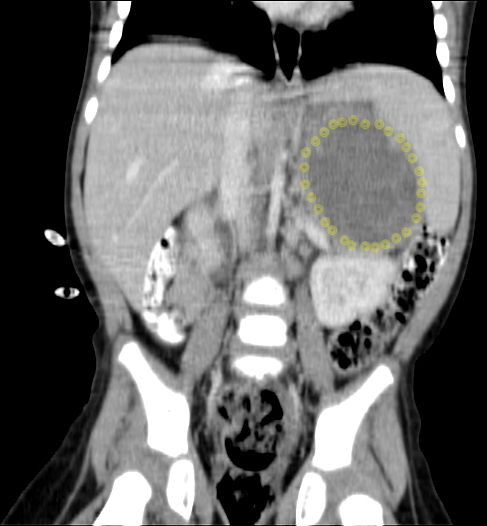

CT (CAT) scan 25 August 2011